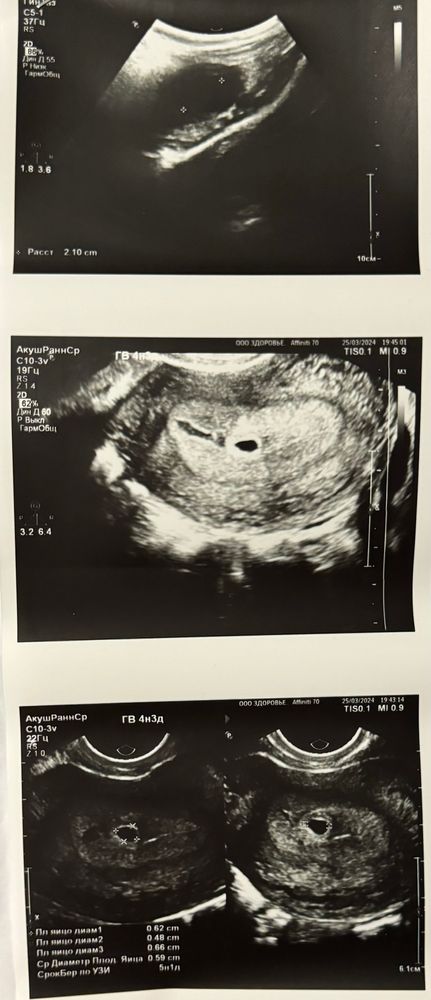

Залина в Зачатие 2 года Сходила на узи😍 Все таки не дотерпела я до 29.03 и сходила на узи сегодня. Акушерских 4н3д, по овуляции 2н6д или 20дпо. Плодное яйцо в матке нашли, размер 6мм🤞🫶🏼 Жду теперь, чтобы послушать сердечко❤️ Посмотрите еще 20 записей на эту тему Отменить Ответить Алиса Прздравляю!🙏🏼😍 я завтра иду на узи 🤞🏼 Очень надеюсь что будет все хорошо🙏🏼 26.03.2024 Ответить Залина Алиса, спасибо ☺️ и я вас поздравляю ❤️все будет хорошо ❤️🫶🏼 26.03.2024 Ответить Алиса Залина, спасибо❤️ тьфу тьфу🙏🏼❤️ 26.03.2024 Ответить Alena Мои поздравления 🎊 🥹 🤰 Я сегодня тоже иду такую красоту смотреть, на сроке 5 недель и 2 дня) Лёгкой беременности Вам 🌸 25.03.2024 Ответить Залина Alena , спасибо ❤️ и Вам 🫶🏼🤞 26.03.2024 Ответить Alena Залина, благодарю 🌺🤗🤰 26.03.2024 Ответить Залина Alena , как сходили?☺️ 26.03.2024 Ответить Alena Залина, только-только написала в дневник 😄😄😄 26.03.2024 Ответить Мария Я Вас поздравляю!!! расскажите когда Вы стали делать тесты не на овуляцию, а на беременность уже🙏🏼 25.03.2024 Ответить Залина Мария, спасибо ☺️я начала с 6дпо😅полосочку увидела на 9дпо 26.03.2024 Ответить Спкя/МФЯ??? 10 дпо динамика тестов Чаты Беременных Выберите чат: Январята-2026 Февралята-2026 Мартята-2026 Апрелята-2026 Майчата-2026 Июнята-2026 Июлята-2026 Августята-2026